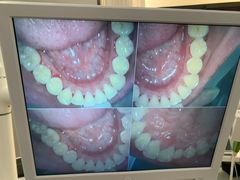

• 牙博士口腔品牌连锁(杨浦店)

• -牙博士口腔品牌连锁(杨浦店)

zqqqqqq | 22-08-05